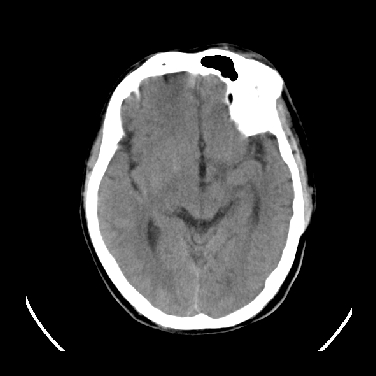

男,45岁,左侧肢体乏力1周。ex:胸片示:两肺团块状、斑片状密度增高影,其内可见小空洞。支纤镜、经皮肺穿示:干酪样物。

结合病史考虑结核性脑炎脑膜炎,伴脑脓肿形成

考虑结核性脑炎脑膜炎,伴脑脓肿形成。

结合病史考虑结核性脑炎脑膜炎,伴脑脓肿形成,囊变转移瘤不除外